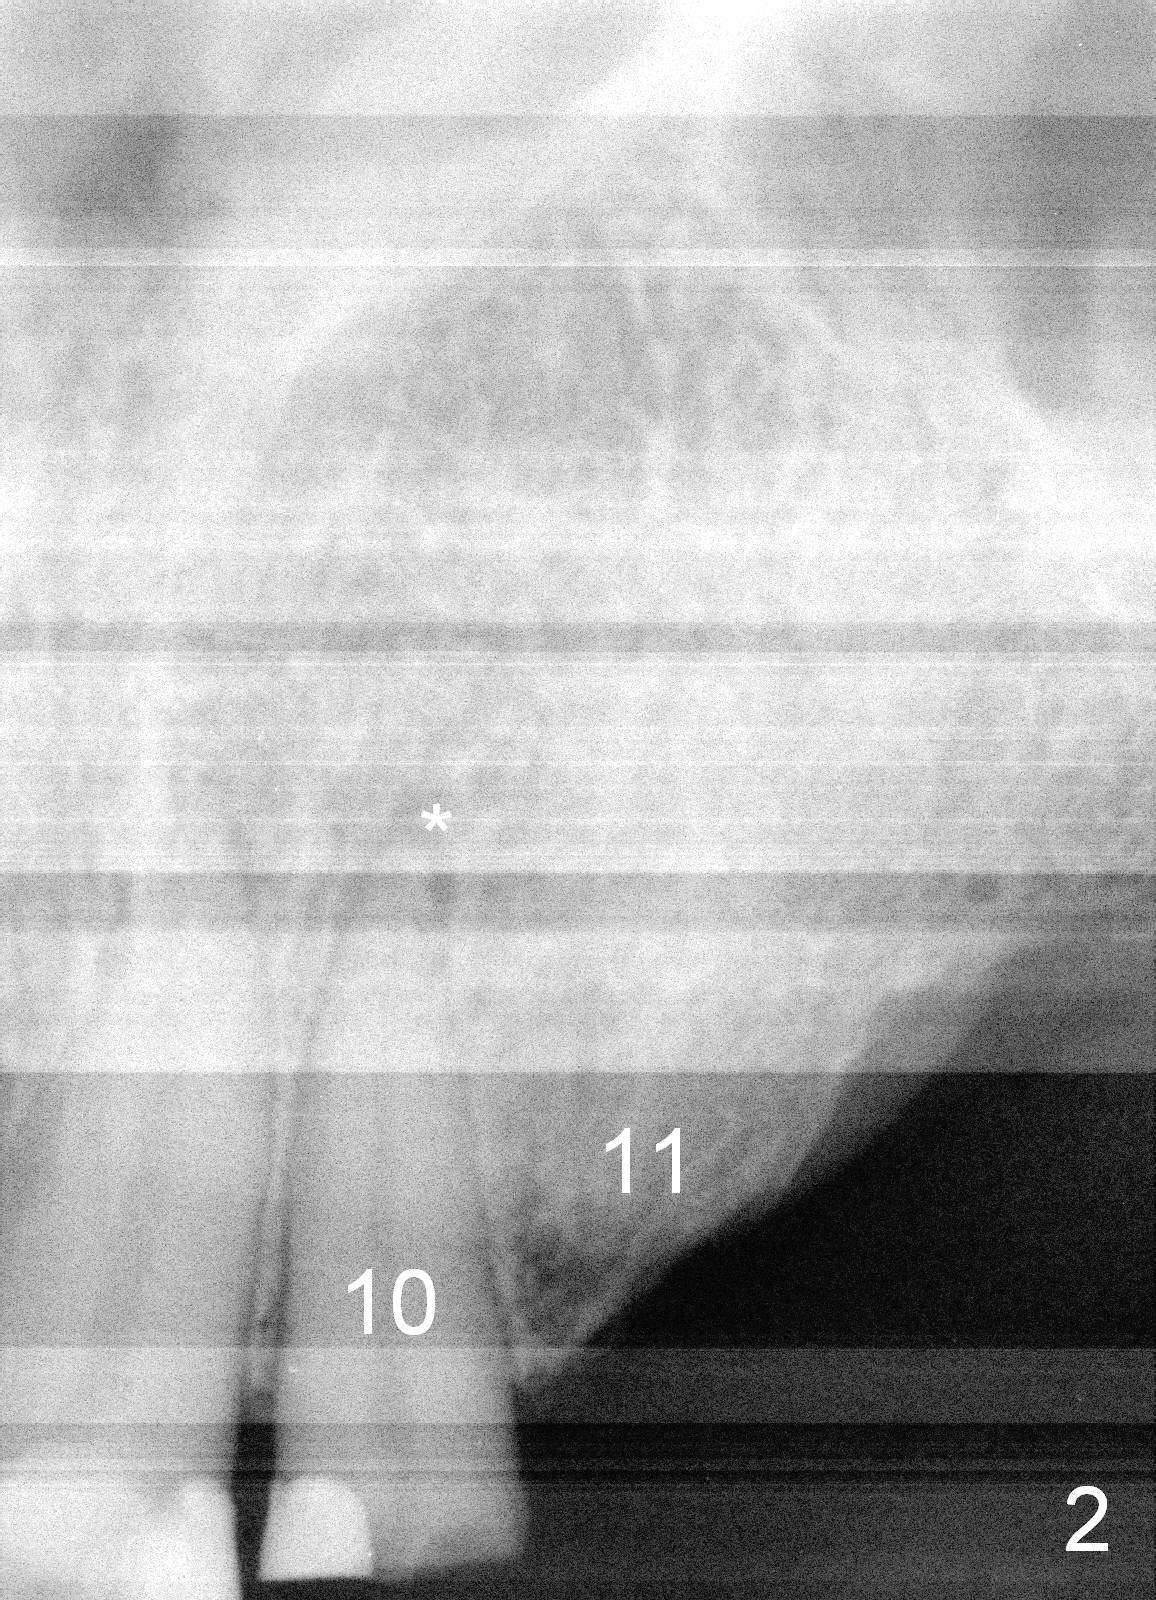

A 70-year-old man (TF) requests implant restoration for the upper left quadrant first (Fig.1), exactly #10 and 11 first (Fig.2-4). There is periapical radiolucency associated with the residual root at #10 (Fig.2 *). Local antibiotic will be Metronidazole. The root of #10 is long and large. The bone at #11 looks loose. Long implants will be placed (Fig.4). Osteotomy preparation should be less.